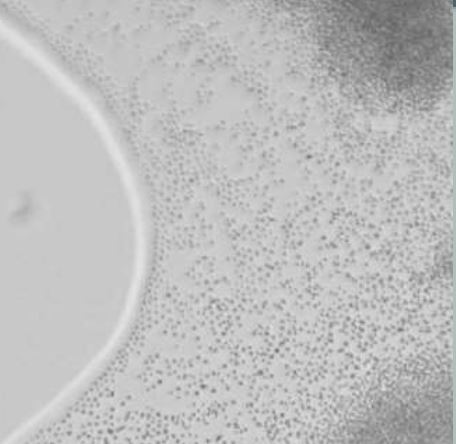

Q

The organism seen here on this cornmeal plate looks similar to Candida glabrata (which will not have spaces between colonies) and it is UREASE positive and produces MELANIN on bird seed agar?

A

Cryptococcus neoformans

Urease positive and also phenol oxidase positive